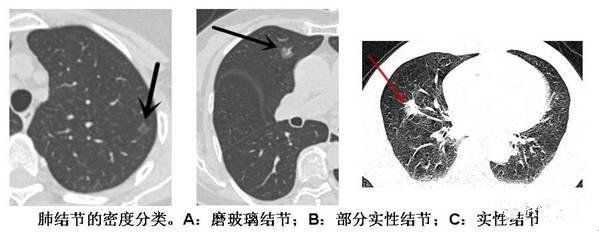

肺结节的分类 (根据密度分类:)

1、实性肺结节:

是一个在CT下呈现白色的高密度的影子,表面光滑小而圆。

2、纯磨玻璃结节:

CT显示的肺内密度稍增高影,但通过病灶仍然能看到肺纹理影,就像透过磨玻璃观察一样。磨玻璃结节在临床上的检出率高。

3、混合磨玻璃结节:

伴有实性成分的混合磨玻璃结节,恶性概率相对较高,易形成肺腺癌,通常由纯毛玻璃结节引起。